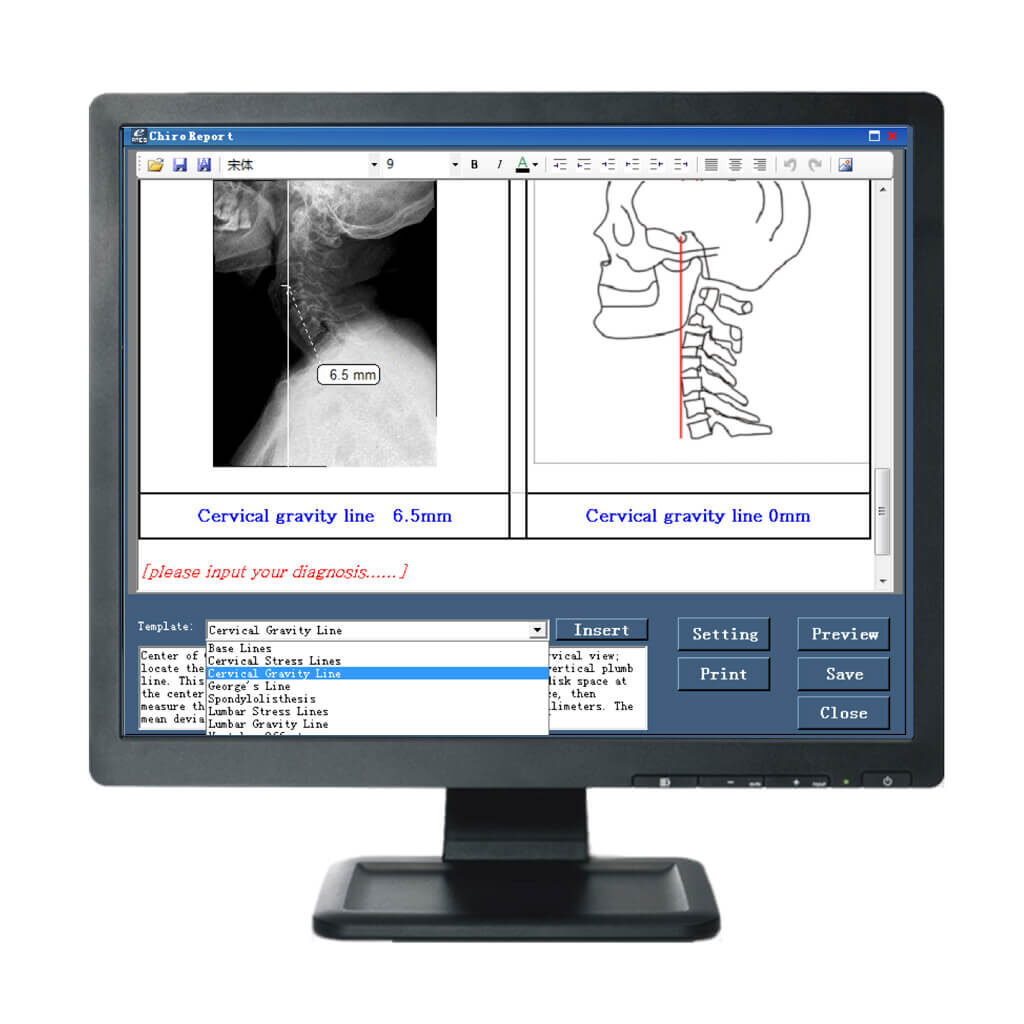

Comprehensive Chiropractic DR Analysis Tools

IQAspire DR panels come with IQView software to combine the superior image quality of Chiropractic DR with world-class Chiropractic Analysis Software.

Easy-to-use acquisition and image measurement tools with full DICOM integration makes IQView a comprehensive image management system for Chiropractic offices.

- User-friendly interface

- Comprehensive Chiropractic Toolset

- DICOM Integration

- Preloaded on laptop or PC

Just Some of the Standard Tools Available